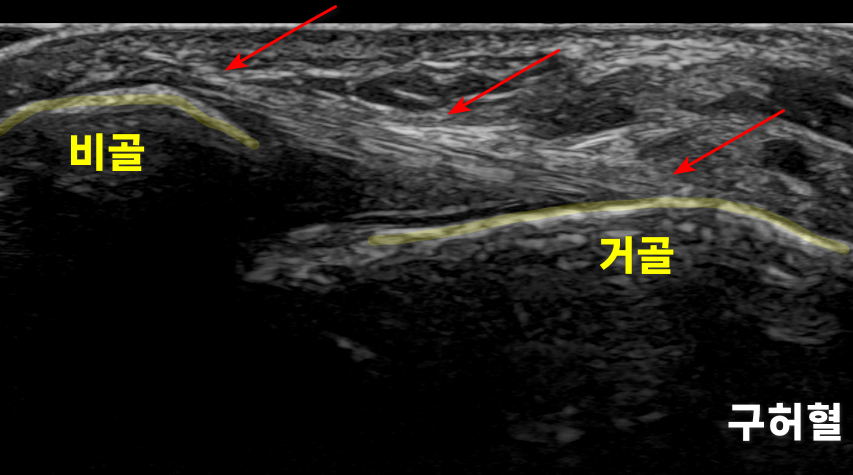

경혈 초음파, 구허혈

한의학에서

발목 염좌를 치료하는

핵심 혈자리는

입니다.

을

초음파로 관찰하면

깊이에 따라서전거비인대,거골, 비골이 보입니다.

위 이미지는

의표준 경혈 초음파 영상인데요.

노란 화살표로

표시한 부분이

앞쪽 거골과 비골을 연결하는입니다.

표준 경혈 초음파와 달리

1) 전거비인대가 두껍게부어있고*

**2)구불구불 주행하고요.*

3) 노란색 화살표 친인대 내부에 까만 틈이 보입니다.